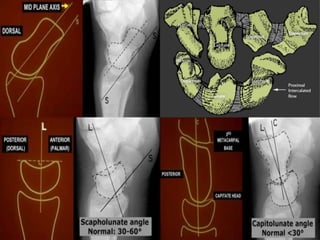

A simple approach is to consider the lunate

which is usually the easiest carpal bone to

visualize on a lateral wrist image. If the

lunate is abnormally tilted in a dorsal

direction on a standard lateral wrist image,

a DISI should be considered. If the lunate is

abnormally tilted in a volar direction a VISI

should be considered. DISI is due to

disruption of the scapho-lunate articulation.

VISI is secondary to disruption of the luno-

triquetral articulation.

DISI deformity.

DISI.

Volar intercalated segmental instability(VISI).

VISI with volar tilting of the lunate.

VISI with luno-triquetrum ligament tear and volar tilting of the lunate.

VISI deformity secondary to Lunotriquetral ligament tear.